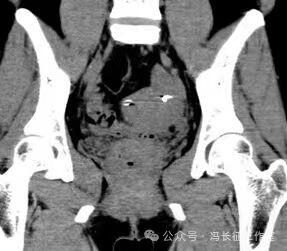

2014年5月在DSA上行输卵管近段介入栓塞术

栓塞前造影也显示双侧输卵管间质部和峡部细长,适合栓塞。于是向双侧输卵管间质部和峡部各栓塞一枚3/2(长2厘米,一端直径小2毫米另一端直径大是3毫米,就是向宝塔一样,有时被称为塔圈)弹簧圈。

栓塞后造影显示弹簧圈固定在双侧输卵管间质部和峡部近段,造影剂未能通过栓塞段,说明输卵管管腔被完全封闭。